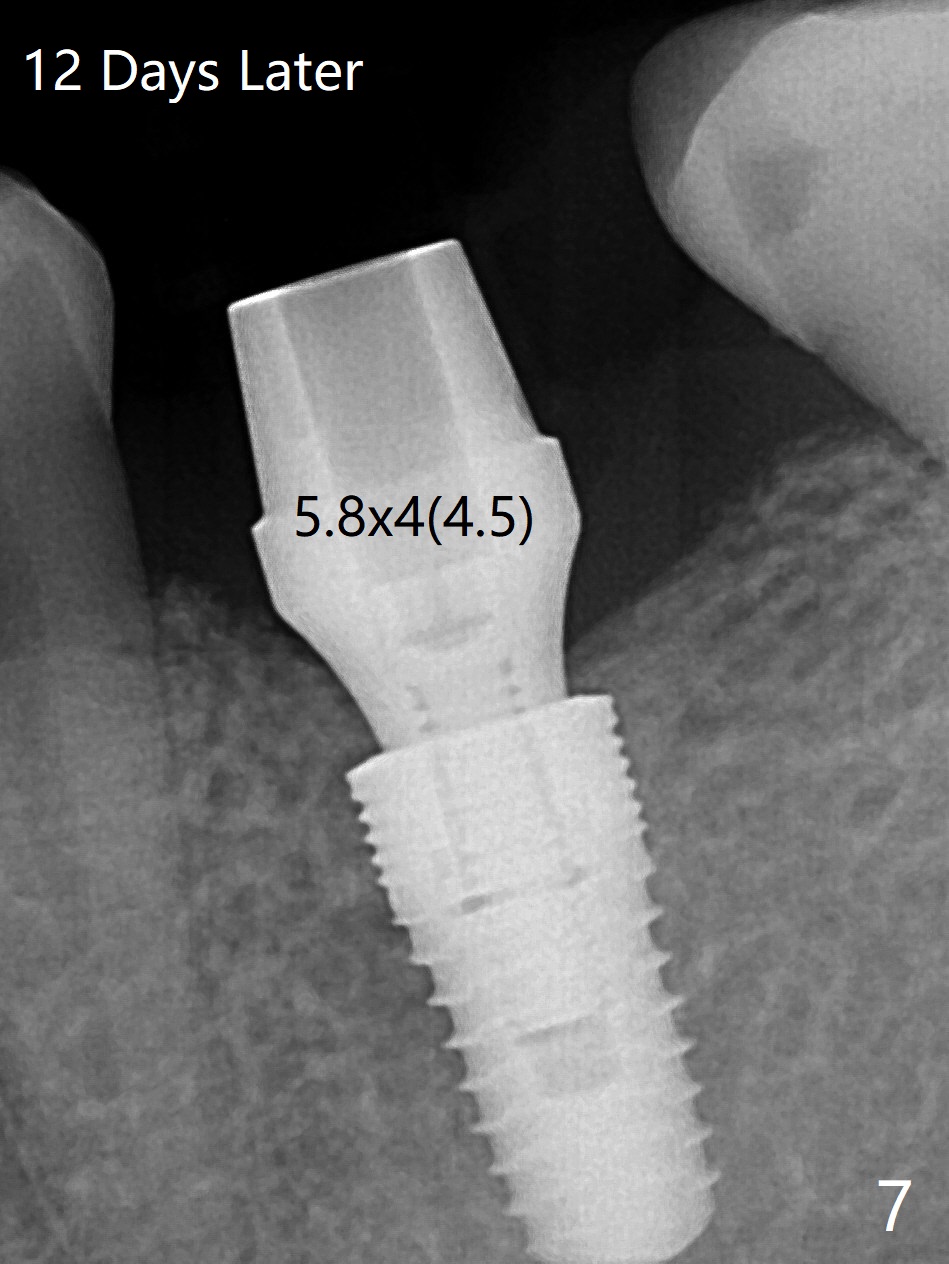

50岁男,左下6牙槽骨宽,但是骨密度低。开始使用导板和小钻头,植体(5x10毫米)扭力大,改用正常钻头,扭力仍高,使用功螺纹后,扭力~35Ncm;使用6毫米profile drill后,放置6x4(2)毫米愈合基台,后者好像与近中牙槽嵴接触(图一:*)。取出基台不顺利,接着放置5x5(3)毫米基台,无法拧紧,取出时,把植体带出来。最后把植体推入钻洞,没有任何扭力,放置愈合帽和Osteogen Plug,缝合(图二,三),牙周敷料,但愿能愈合。在骨质密度低时,放置不合适基台(太宽,太短),可能造成植体松动,脱落,失败。术后十二天牙周敷料脱落,伤口正在愈合(图四(曾经使用环形刀))。术后四个月植体仿佛已经整合(图五),切开放置6.2x5(3)毫米愈合基台,好像与近中牙槽嵴接触太紧(图六)。12天后放置修复基台,似乎就位(图七),其实我们使用取模帽放置基台,非常容易,取模也方便。基台牙冠就位也容易(图八)。螺丝拧紧25Ncm/厂家建议35Ncm。